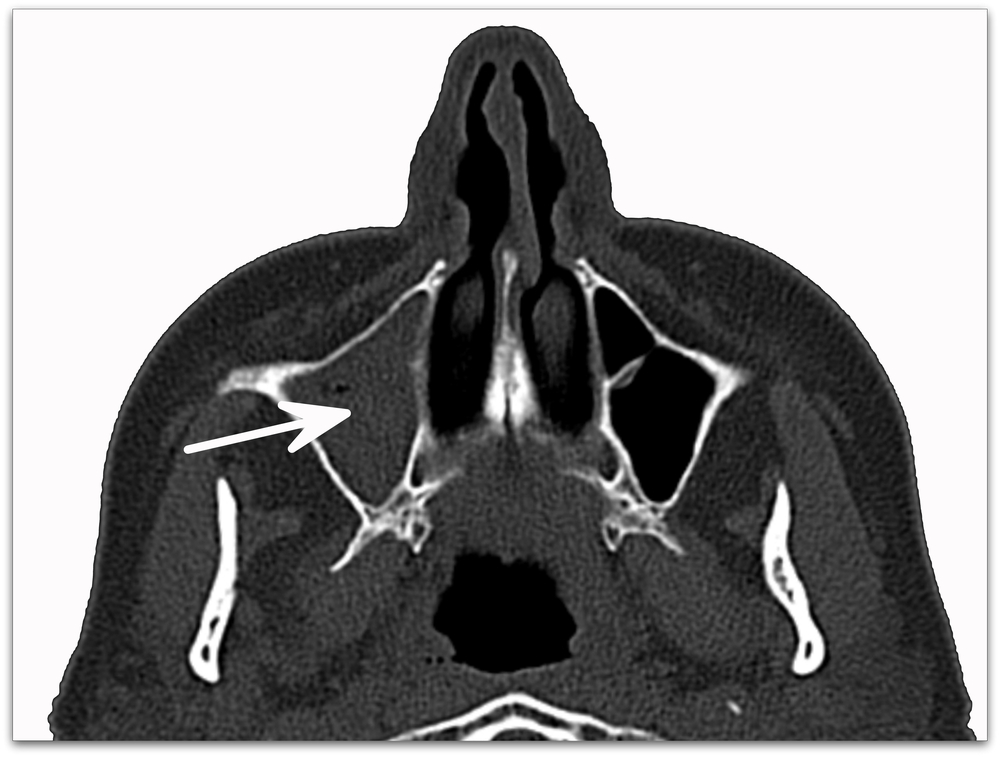

В большинстве случаев для изучения строения и выявления патологических изменений в полости носа и околоносовых синусах применяется коронарная проекция. При этом просвечивание начинается от передних отделов лобного синуса и заканчивается в зоне задней части клиновидной пазухи. Оно проводится в режимах «костного» и мягкотканного» окна с толщиной среза 0,5 см.

- аксиальной;

Аксиальная проекция используется для уточнения границ распространения патологического процесса за пределы носа и его синусов (в глазницы и полость черепа). Она проводится в плоскости, расположенной параллельно твердому небу, начиная от нижней стенки гайморовой пазухи до верхних отделов лобной.